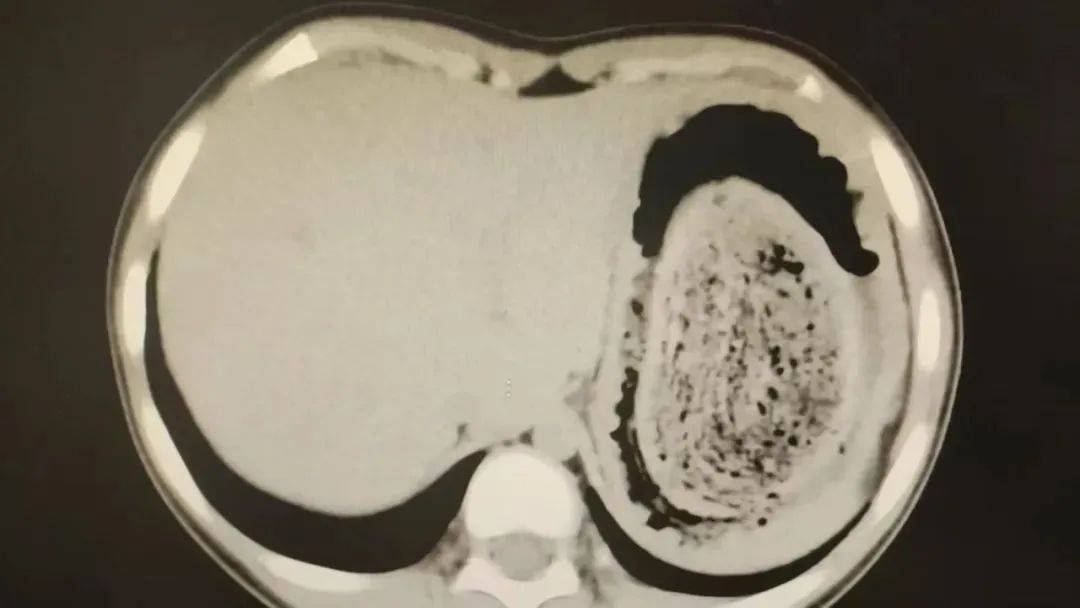

10岁女孩园园(化名)因持续3天的上腹痛伴呕吐被紧急送医皇冠信用网登2。影像学检查结果显示,她的胃部存在一个巨大的团块状阴影,初步怀疑为异物堵塞。据家长回忆,园园从1年前开始就有偷偷吃头发的习惯,但家人并未重视,直到这次症状严重才意识到问题的严重性。

在胃镜帮助下,妮妮胃里的情况逐渐明了皇冠信用网登2。一个滚圆黑色的毛发球混合着食物残渣占据整个胃腔,这些头发相互缠绕形成一个实心的“发石”,此外胃里还有一个鸡蛋大小的溃疡。

症结找到了,就是这个巨大的发石导致妮妮出现营养不良、贫血和闭经,当务之急就是取出“发石”,给胃进行“大扫除”皇冠信用网登2。

“发石”混杂着食物残渣,就像一个黑色的小西瓜皇冠信用网登2。由于整个“发石”体积太大,为避免损伤胃壁,医生借助手术工具将“发石”切割、分解,再小心翼翼地分块取出。整场手术持续2个多小时,最终取出4斤头发碎片。